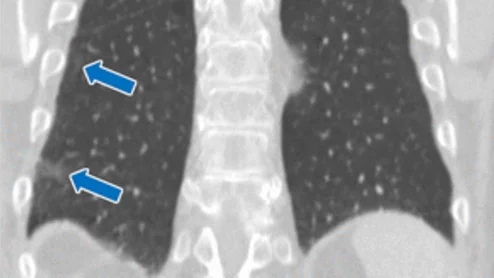

Decreased screening rates among different subgroups highlight the ongoing need for outreach strategies that target vulnerable populations, experts contend.